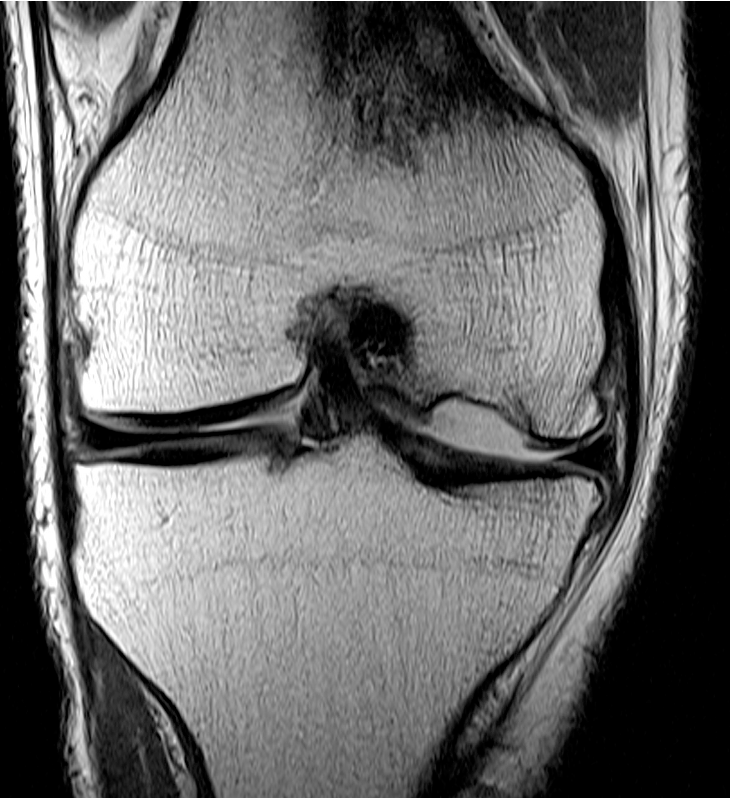

MFC OCD on presentation T2 image 6 months later

T1 sagittal on presentation T1 sagittal six months later

Stable lesion with no cysts Stable lesion with cysts